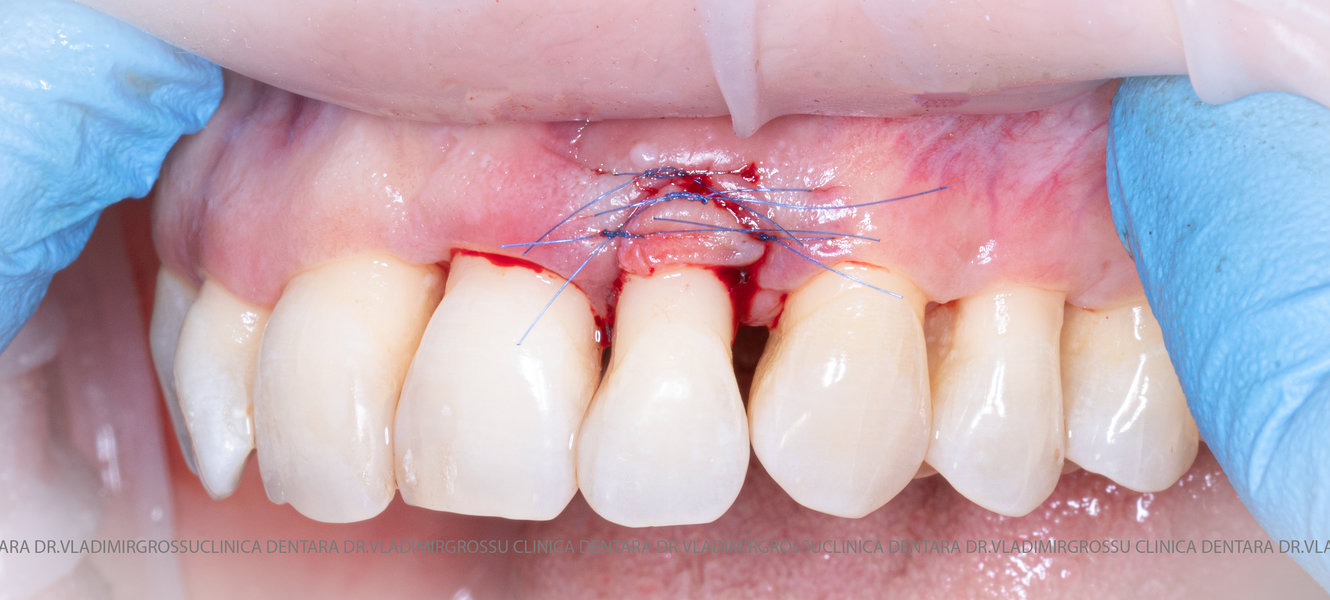

Aditia gingivală este o procedură chirurgicală ce corectează diverse probleme estetice și funcționale, cum ar fi recesiunea gingivală. În implantologia modernă, aditia de țesut moale este utilizată aproape în fiecare intervenție de inserție a implantului dentar pentru a asigura un aspect estetic natural și o bună integrare a implantului în cavitatea bucală.

Adiția osoasă are un rol crucial pentru poziționarea corectă și stabilă a implanturilor dentare. Clinica stomatologică Dr. Grossu din Chișinău promovează o abordare chirurgicală estetică și predictibilă, adaptată fiecărui caz în parte.

Medicii noștri au o vastă experiență atât în chirurgia estetică, cât și în protezarea cu un grad înalt de naturalitate, ceea ce ne permite să gestionăm cu succes și cele mai complexe cazuri.